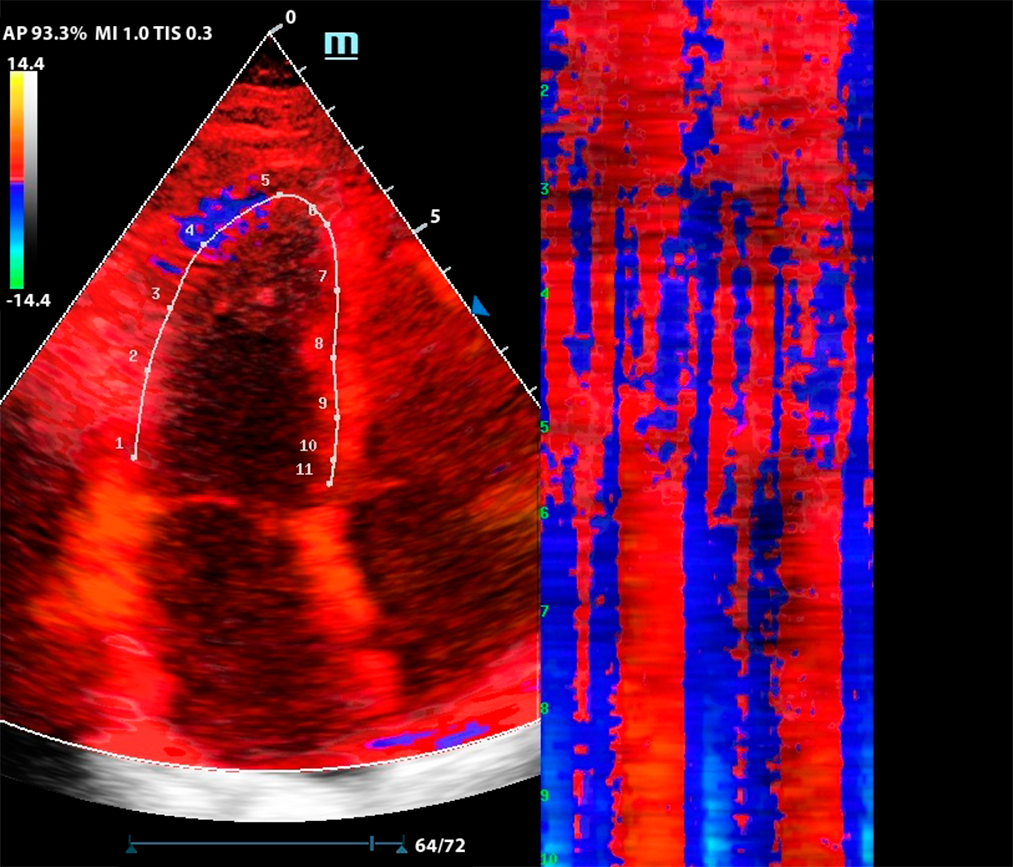

Функция изогнутого М-режима особенно интересна в комбинации с тканевым допплером (TDI). Оконтуривание миокарда в цветовой карте TDI позволяет оценить кинетику левого желудочка посегментно, в виде цветовой карты на графике Free Xros CM.

Метод разворачивает левый желудочек в плоскую палитру движений за счет окраски тканевого допплера, это позволяет сравнить кинетику в каждом моменте цикла сокращения и расслабления.